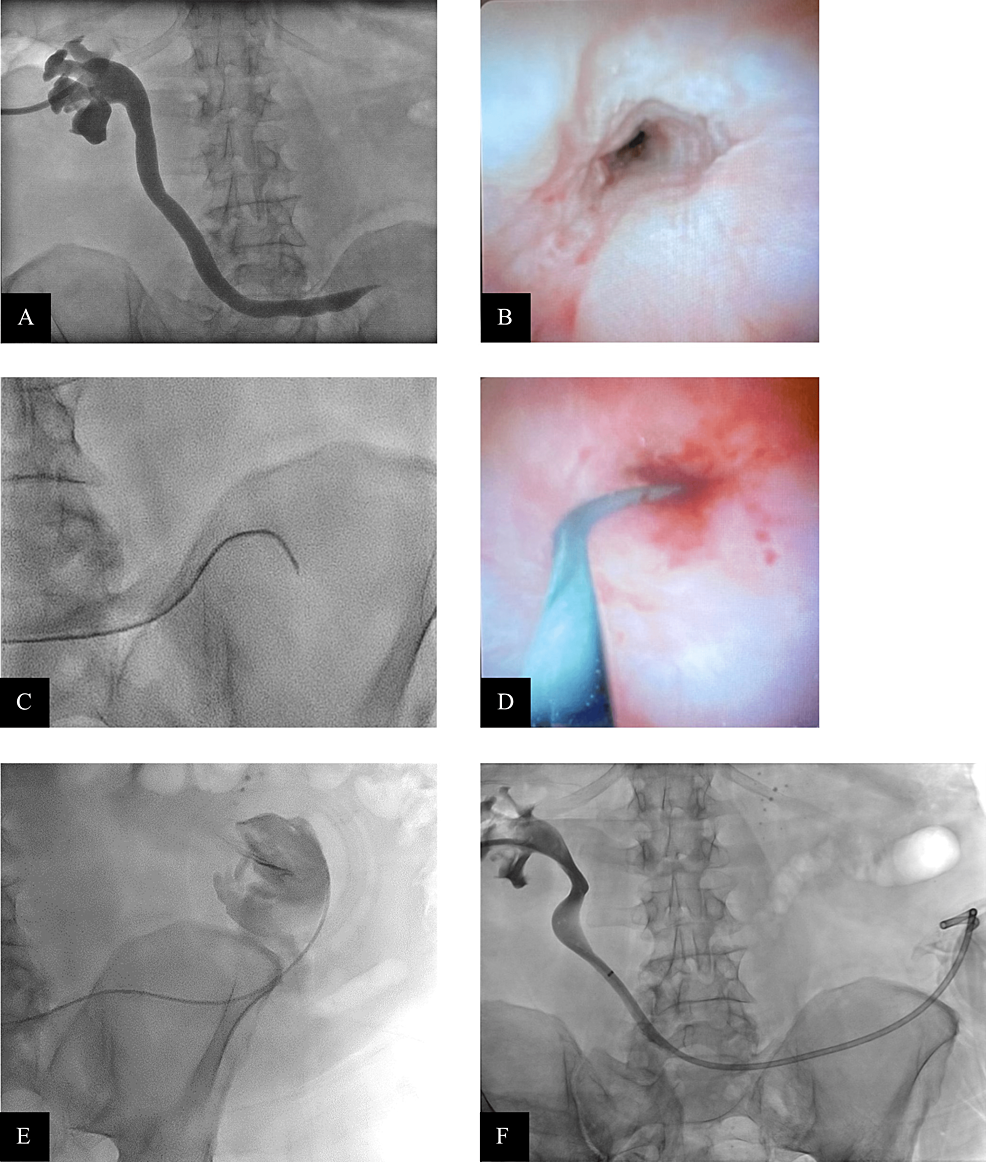

Fluoroscopyguided balloon dilation of a proximal urethral stricture Ureteral Balloon Dilation Procedure In this contemporary review balloon dilation of the ureter before endoscopic treatment of stone disease was associated with a high success rate and few. The most common initial management of benign ureteral strictures is balloon dilation, followed by stent placement for 4. In this contemporary review balloon dilation of the ureter before endoscopic treatment of stone disease was associated with. Ureteral Balloon Dilation Procedure.